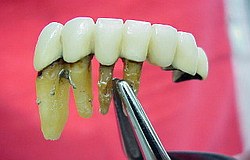

Die Nervnadel wird in den Nervkanal eingeführt

Wird nichts mehr empfunden so ist er tot und das tote Gewebe muss schnellstens aus dem Zahn entfernt werden (Wurzelkanalreinigung) bevor es im Zahn verfault und zu starken Schmerzen bis hin zur dicken Backe (Zyste) führt. Obwohl im Bild zur Verdeutlichung dargestellt ist eine Aufbereitung des Wurzelkanals (Nervnadel ragt über Wurzel hinaus ) über die Wurzel in den Kieferknochen bei der Zahnwurzelbehandlung natürlich nicht erwünscht. Um dies zu vermeiden müssen während der Wurzelbehandlung Röntgenaufnahmen angefertigt werden, die die ungefähre Länge der Wurzel berechnen lassen. Besser noch lässt sich die Länge der Wurzel elektronisch bestimmen .(Auf Wunsch Privatleistung). Ist die Wurzel an Ihrem Ende weit geöffnet kann es trotz aller Vorsicht zu einem ungewünschten Überaufbereiten und zu einer Überfüllung der Wurzel kommen. Dies beeinträchtigt dann oft den Erfolg. html Text zum Ausdrucken als pdf Datei. Falls über die Wurzelspitze hinaus in den umliegenden Knochen bereits Eiter aufgetreten ist und dieser den Knochen um den Zahn auflöst (das sieht man im Röntgenbild), so muss die infektiöse Wurzelspitze und die darum liegende Zyste entfernt werden .Im Prinzip ähnlich einem Pickel ausdrücken. Sobald der Druck (Eiter) dann heraus kann, geht sehr schnell der Schmerz bzw. auch die dicke Backe zurück. Der Vorgang nennt sich Wurzelresektion oder Apektomie. Die moderne Wurzelbehandlung umfasst Nickel-Titan-Feilen mit drehmomentregulierten Motoren gegen Instrumentenbruch, elektronische Längenmessung, Langzeit-provisorische Wurzelfüllungen mit provisorischen Langzeit-Füllungen. Alles leider Dinge die nicht in der Kassenleistung enthalten sind. So bleiben für den Patienten Kosten von ca. 60-480 EUR (je nach Schwierigkeit ) pro Kanal Aus manchen spezialisierten Prominentenpraxen wurde mir schon von Preisen bis zu 1200 EUR pro Kanal berichtet.